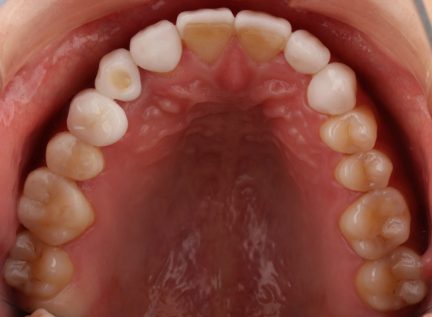

Classe I, morsure bord à bord, espacement, diastème

État initial

- Il s'agit d'un cas d'orthodontie combinée à une réparation esthétique.

- Il était nécessaire d'améliorer l'occlusion et la répartition de l'espace grâce à Invisalign et d'améliorer la forme et la beauté des dents du patient grâce à une restauration esthétique.

- Avant le traitement orthodontique, le patient a utilisé la conception esthétique DSD pour répartir l'espace, et l'espace dispersé en dehors de la zone esthétique a été ajusté par le mouvement proximal de la dent postérieure.